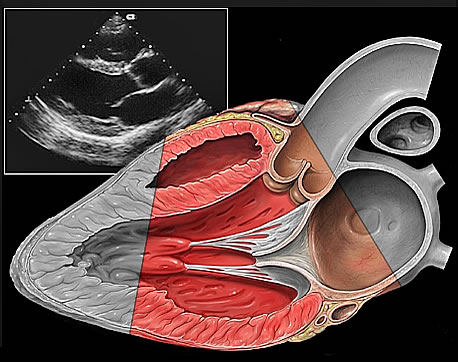

Echokardiografia przezklatkowa (TTE – transthoracic echocardiography)

To badanie wykonywane poprzez ścianę klatki piersiowej, umożliwiające

obrazowanie serca w badaniu:

- dwuwymiarowym (2D) - umożliwiającym pomiary powierzchni

i objętości oraz obliczenie frakcji wyrzutowej;